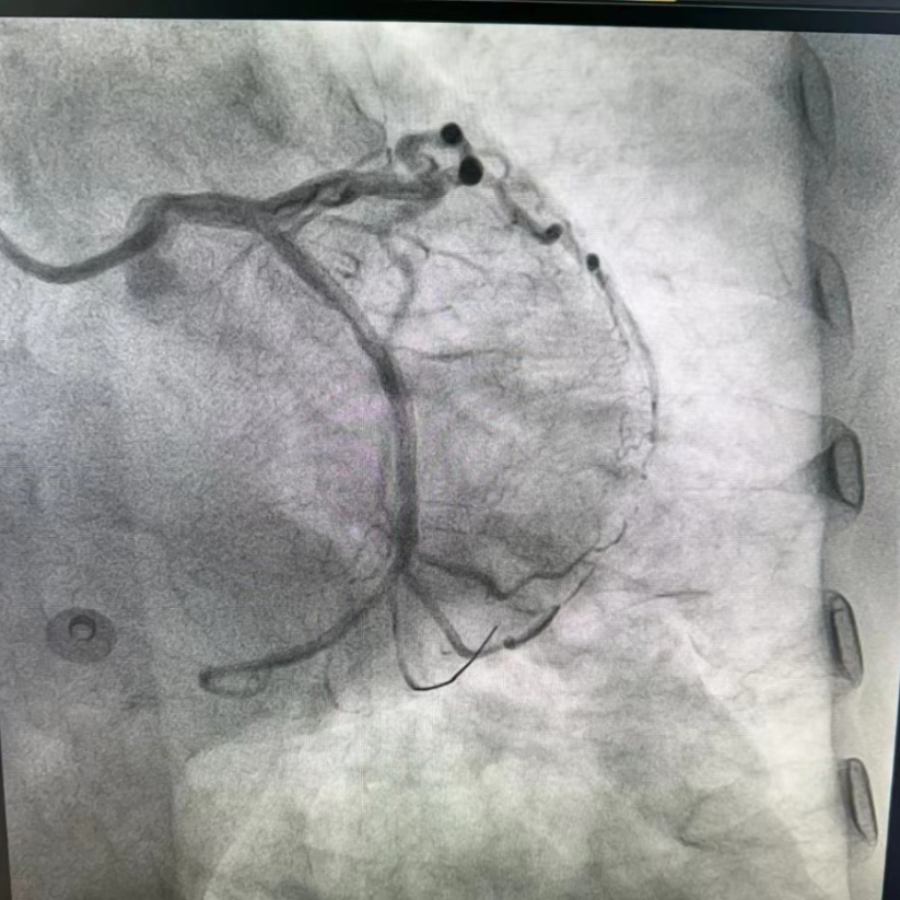

陈奶奶入院后,心脏康复科团队立即与陈奶奶家属沟通病情、排除禁忌症后,随即为陈奶奶行冠状动脉造影,造影发现陈奶奶左冠优势型,LCX中段完全闭塞,急性心肌梗死诊断明确,经家属知情并同意后在回旋支植入支架一枚,复查造影,见支架扩张充分,血流动力学稳定。经过1个多小时,手术圆满完成。术后常规按冠心病二级预防治疗,现陈奶奶恢复良好。

冠脉造影被称为确诊冠心病的“金标准”,它是利用血管造影机来对患者的冠状动脉进行检查,将透明的造影剂快速注入血流,之后血管在X线的照射下显影。在显影下可以评估冠状动脉血管的走向、数量以及畸形等异常表现,可以及时发现冠状动脉内是否存在病变、病变严重程度以及范围。